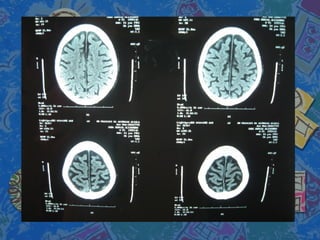

Se solicita TAC craneal con atrofiaSe solicita TAC craneal con atrofia

corticosubcotical cerebral ycorticosubcotical cerebral y

cerebelosacerebelosa

Se solicita TACcraneal con atrofiaSe solicita TAC craneal con atrofia corticosubcotical cerebral ycorticosubcotical cerebral y cerebelosacerebelosa